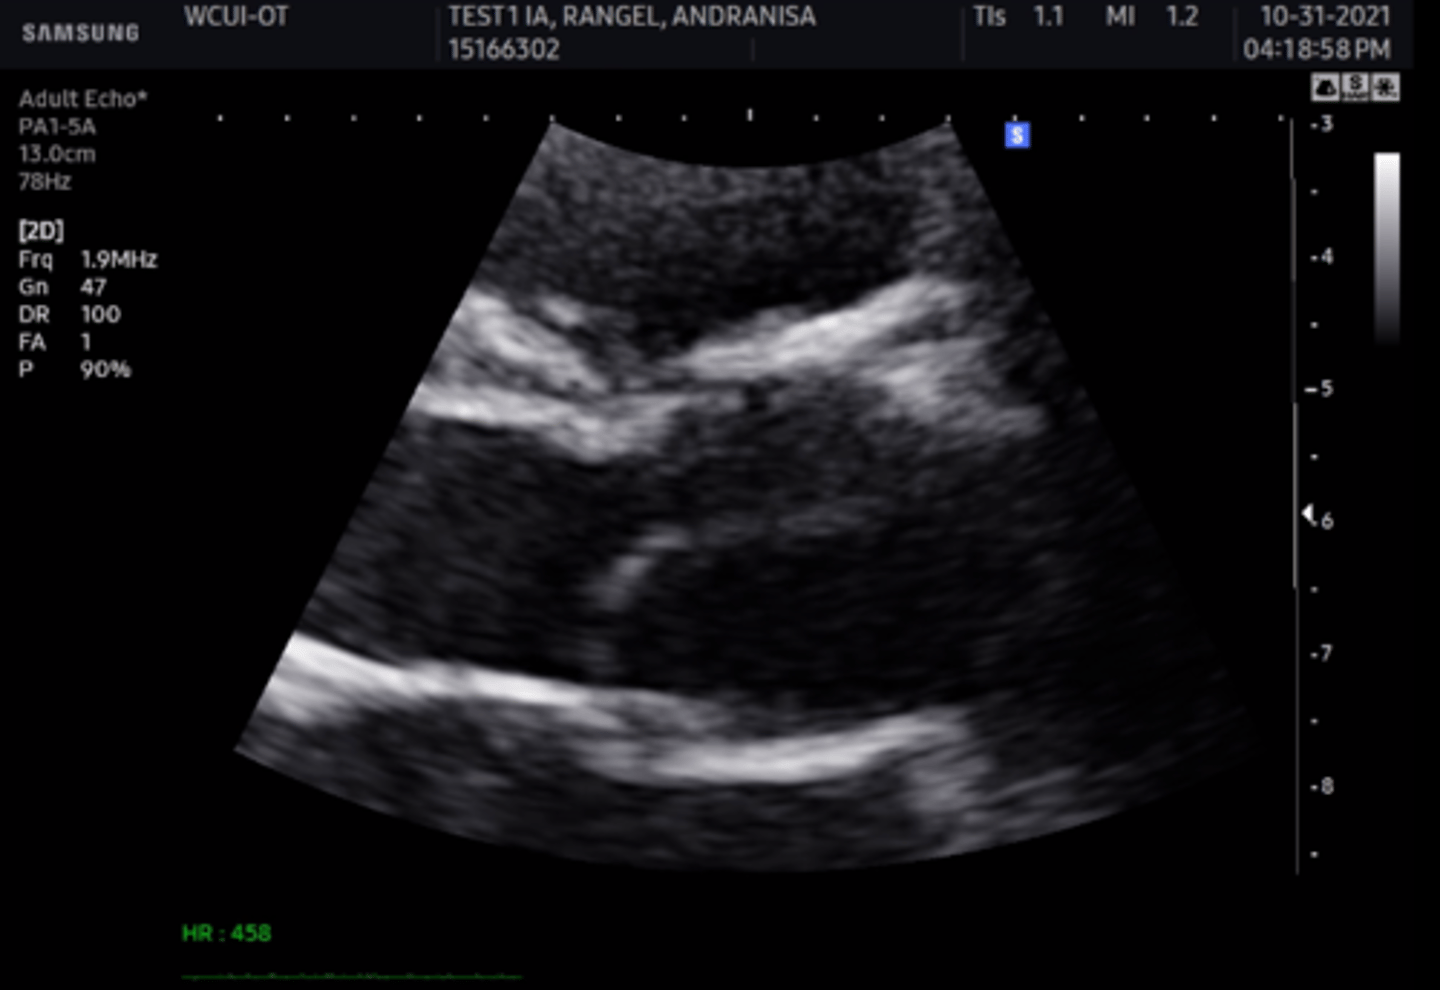

anterior mitral valve leaflet

top leaflet

posterior mitral valve leaflet

bottom leaflet

anterior tricuspid valve leaflet

left leaflet

medial/septal tricuspid valve leaflet

right leaflet